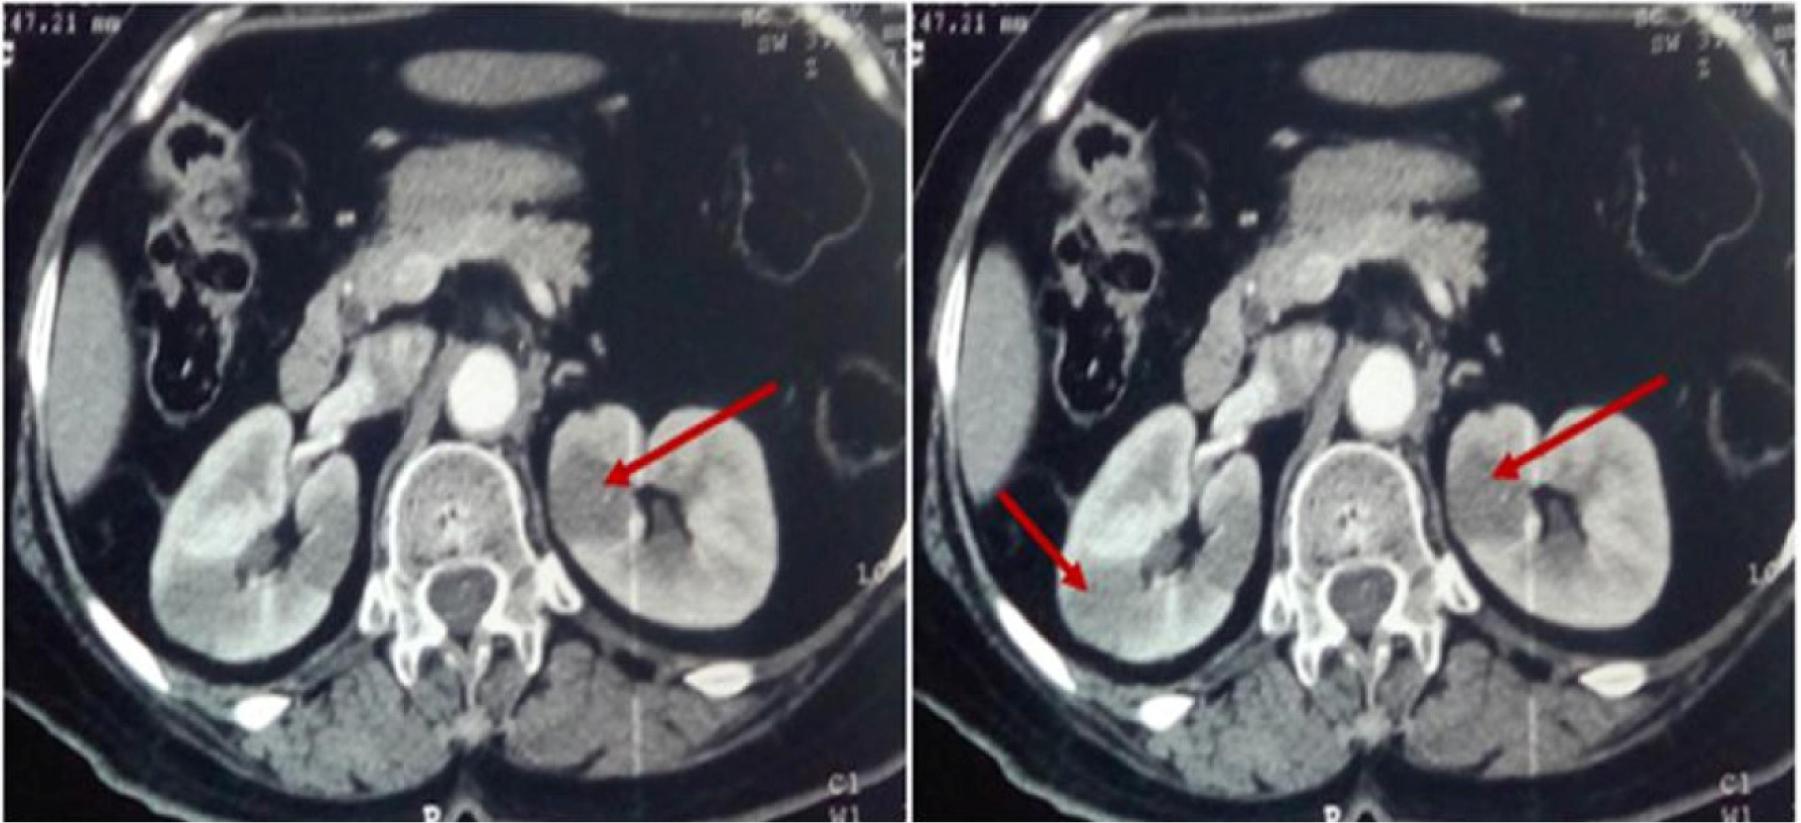

In 2005, a 66-year-old female consulted for nasal obstruction and rhinorrhea evolving since 8 months. Clinical examination documented a left polypoid nasal lesion; tumor biopsy revealed an ACC. The patient underwent surgery followed by radiation therapy (64Gy). During follow-up, after 8 years, the patient presented a distant recurrence of the disease with solitaire lung metastases. No local relapse was observed. Metastasectomy of the lesion was practiced with economic margins, followed by radiotherapy (60Gy). In April 2019, the patient presented at the hospital for a pain in the right flank. No other symptoms were reported. Computed tomography (CT) of the abdomen showed multiple hypodense nodular lesions of the two kidneys, the larger one measuring 30 × 25 × 40 mm in the right kidney (Figure 1).

Figure 1: CT scan showing bilateral renal lesions.